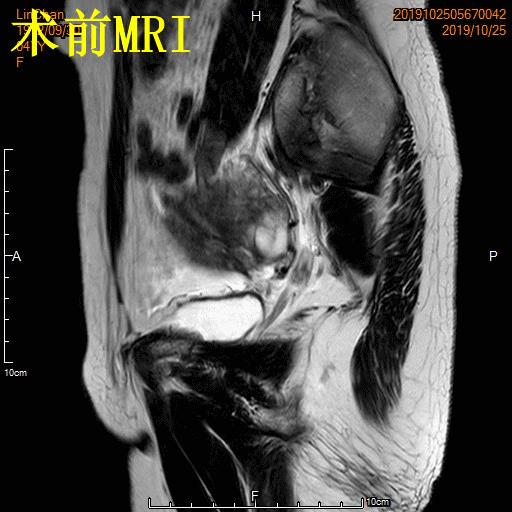

- 术前MRI显示子宫明显增大,病灶主要位于子宫前壁

术前MRI显示子宫明显增大,病灶主要位于子宫前壁

- 术前MRI检查显示子宫明显增大。

术前MRI检查显示子宫明显增大

- 术前彩超、磁共振检查显示子宫明显增大,子宫前壁可见弥漫型子宫腺肌症病灶,合并粘膜下、肌壁间子宫肌瘤。

横断位

冠状位

矢状位